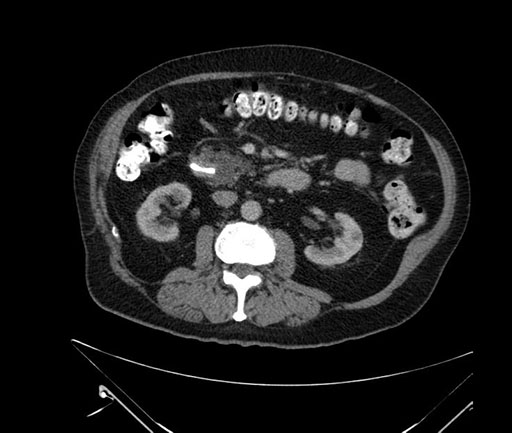

Axial - stented